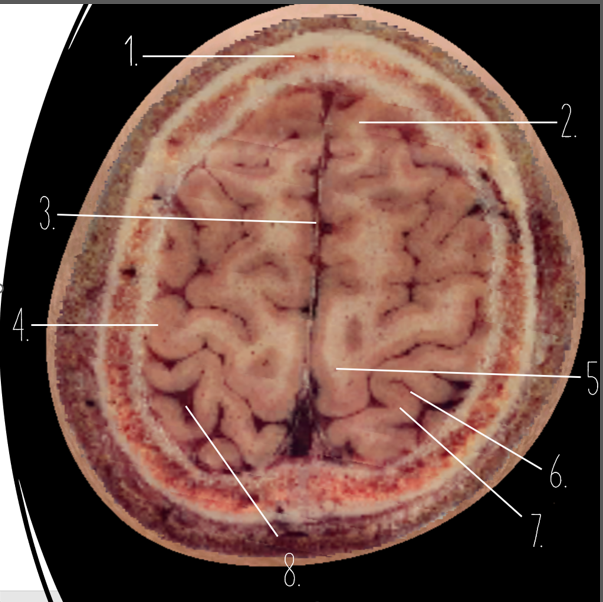

1

Frontal Bone

2

Frontal Lobe

3?

Falx Cerebri

4?

Gray Matter

5?

White Matter

6?

Sulcus

7?

Gyrus

8?

Fissure